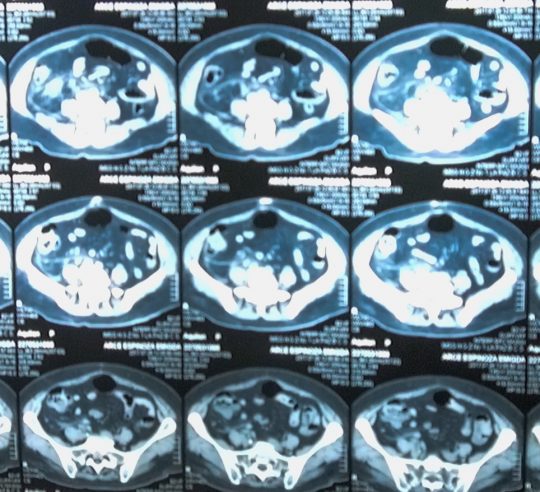

Para el diagnóstico se pueden realizar diversos estudios dentro de los que se encuentran la toma de líquido cefalorraquídeo, electroencefalograma, tomografía axial computarizada y resonancia magnética.